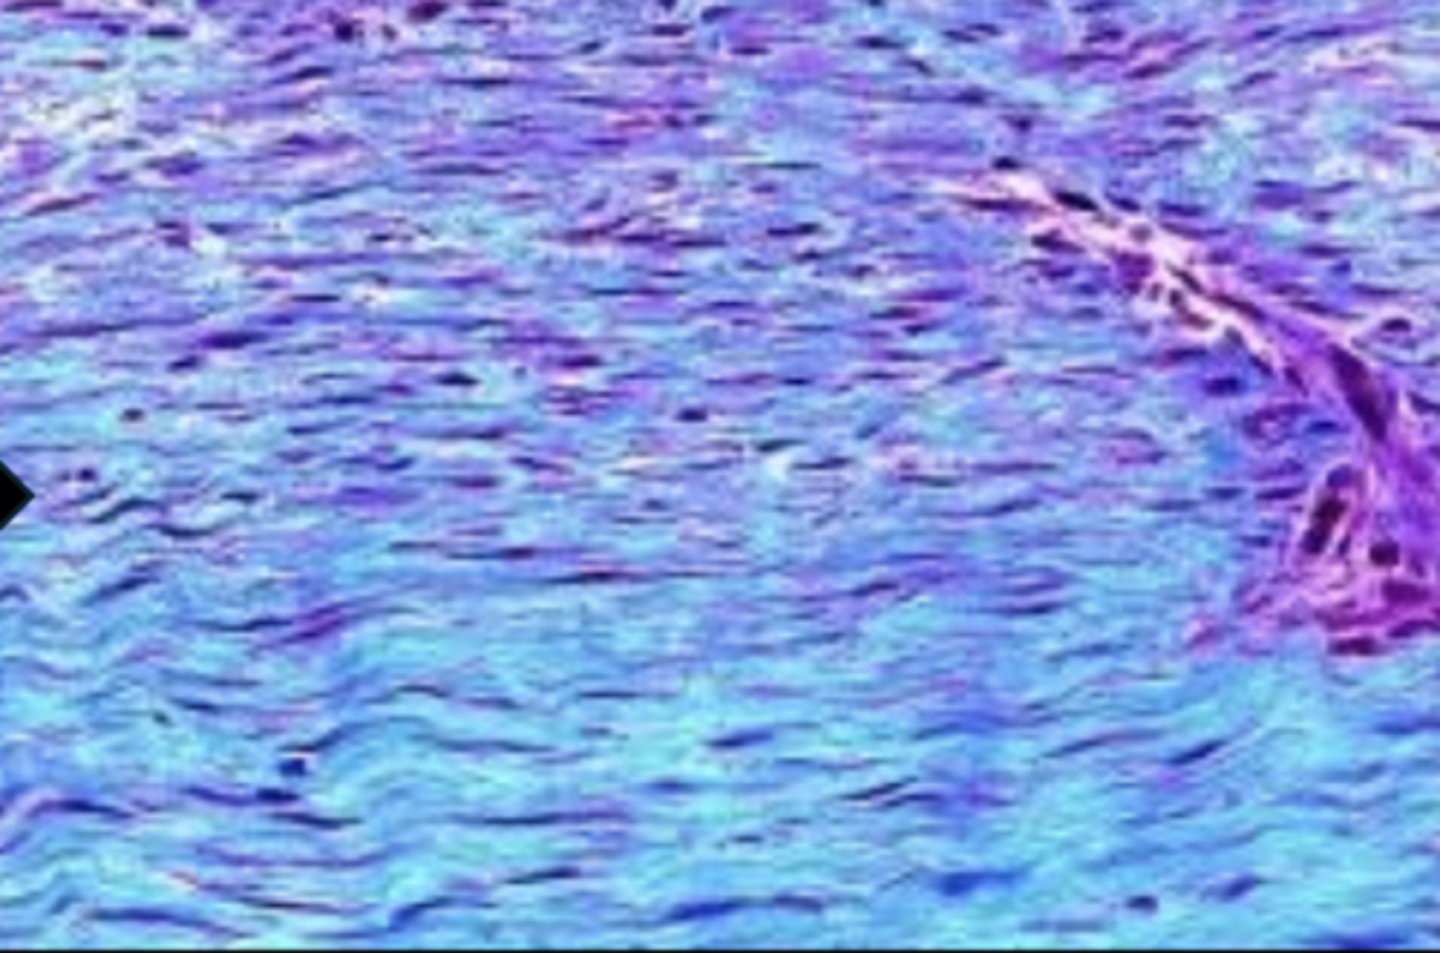

granulation tissue maturing into fibrous connective tissue